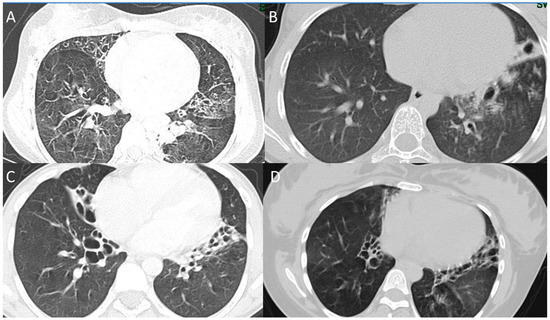

The CXR and CT chest findings of the enrolled patients are summarized in Table 3. CXRs were conducted on all 28 patients, and chest CTs were performed on 17 of them. The CXRs showed lobar collapse/consolidation in 19 (67.9%) and peribronchial wall thickening in 24 (85.7%) of the patients. The most common findings on chest CT scans were consolidation (seen in all patients), mucus plugging (seen in 95%), bronchiectasis (seen in 77%), and ground-glass density (seen in 36%). In patients with bronchiectasis, the most commonly affected lobes were the right lower lobe (88%), left lower lobe (76%), right middle lobe (65%), left upper lobe (47%), and right upper lobe (29%). Selected CT chest findings for some of the enrolled patients are shown in Figure 3.

Figure 3.

CT scans chest findings (patients 17, 12, 16, and 7). (A) CT scan of patient 17 (14-year-old female with RSPH9 gene mutation) shows mosaics pattern with bilateral bronchiectasis. (B) CT scan of the patient 13 (13-year-old female with TP73 gene mutation) shows left lower lobe cystic bronchiectasis. (C) CT scan of the patient 16 (15-year-old male with DNAH5 gene mutation) shows bilateral cystic bronchiectasis. (D) CT scan of the patient 8 (25-year-old female with DNAH5 gene mutation) shows mosaic attenuation with bilateral bronchiectasis.